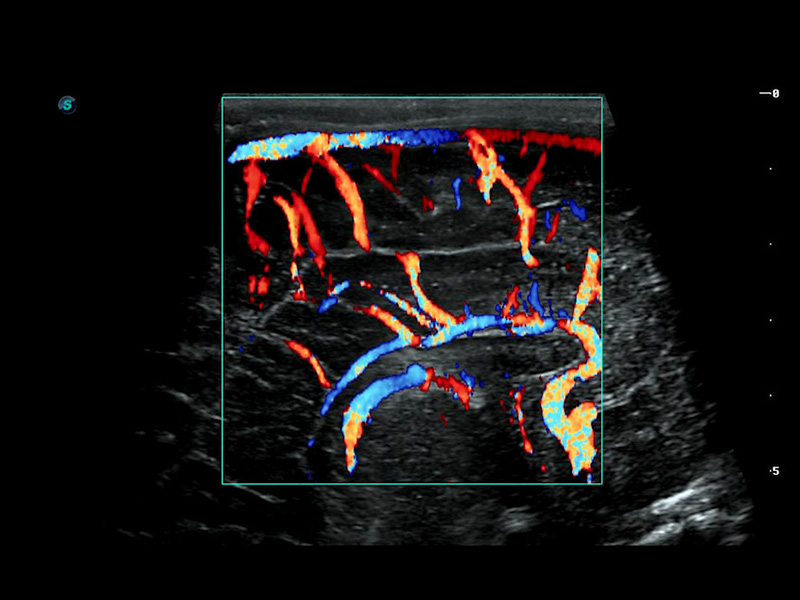

Micro F

Micro F bietet eine innovative Methode, um den sichtbaren Fluss in der Ultraschallbildgebung zu erweitern, insbesondere um den langsamen Fluss kleiner Gefäße sichtbar zu machen. Durch die Verwendung eines fortschrittlichen adaptiven Filters und die Akkumulation von zeitlichen und räumlichen Signalen kann Micro F den geringen Blutfluss effektiv von der Bewegung umgebendem Gewebe unterscheiden und die Hämodynamik mit höherer Empfindlichkeit und räumlicher Auflösung darstellen.

• Zervikales schlecht differenziertes Karzinom mit Micro F

• Fetale Pericallosal-Arterie mit Micro F

• Fetale einseitige Kleinhirnhypoplasie mit Micro F

• Fetaler Leberblutfluss mit Micro F